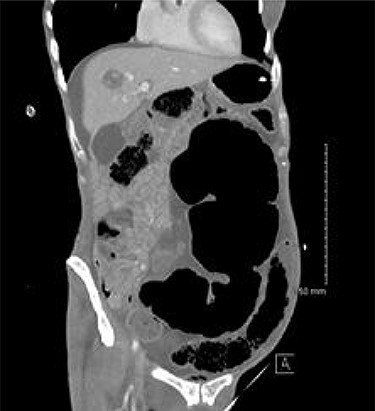

A 54-year-old female presented to the emergency department with a 2-day history of crampy abdominal pain, distension and absolute constipation. She had a history of chronic constipation but no other significant medical history. Her abdomen was diffusely tender and grossly distended on examination, with abdominal X-ray showing the ‘coffee bean’ appearance of SV. Computed tomography (CT) of the abdomen was performed which confirmed the presence of SV without evidence of ischaemia or perforation (Fig. 1). CV was not appreciated on this scan. The patient was brought to the endoscopy unit and underwent sigmoidoscopic decompression. Following this, the patient returned to the ward for observation.

CT appearance suggestive of SV with collapsed right colon and no appreciable CV.